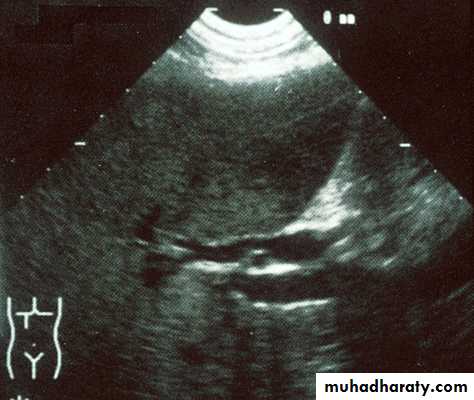

Normal liver US